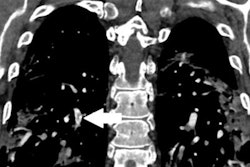

For the project, the group evaluated 21,802 chest, abdomen, and pelvis CT scans and CT pulmonary angiograms (CTPA) acquired from January 2015 to October 2017. After analyzing the data and discussing the information with radiologists and CT technologists, the researchers pinpointed three areas for improvement and then developed the following initiatives to address each one:

- Implement a size-specific protocol for CTPA. The researchers decreased the CTPA exam peak tube voltage from 120 kV to 100 kV for patients with a body mass index (BMI) of less than 25.